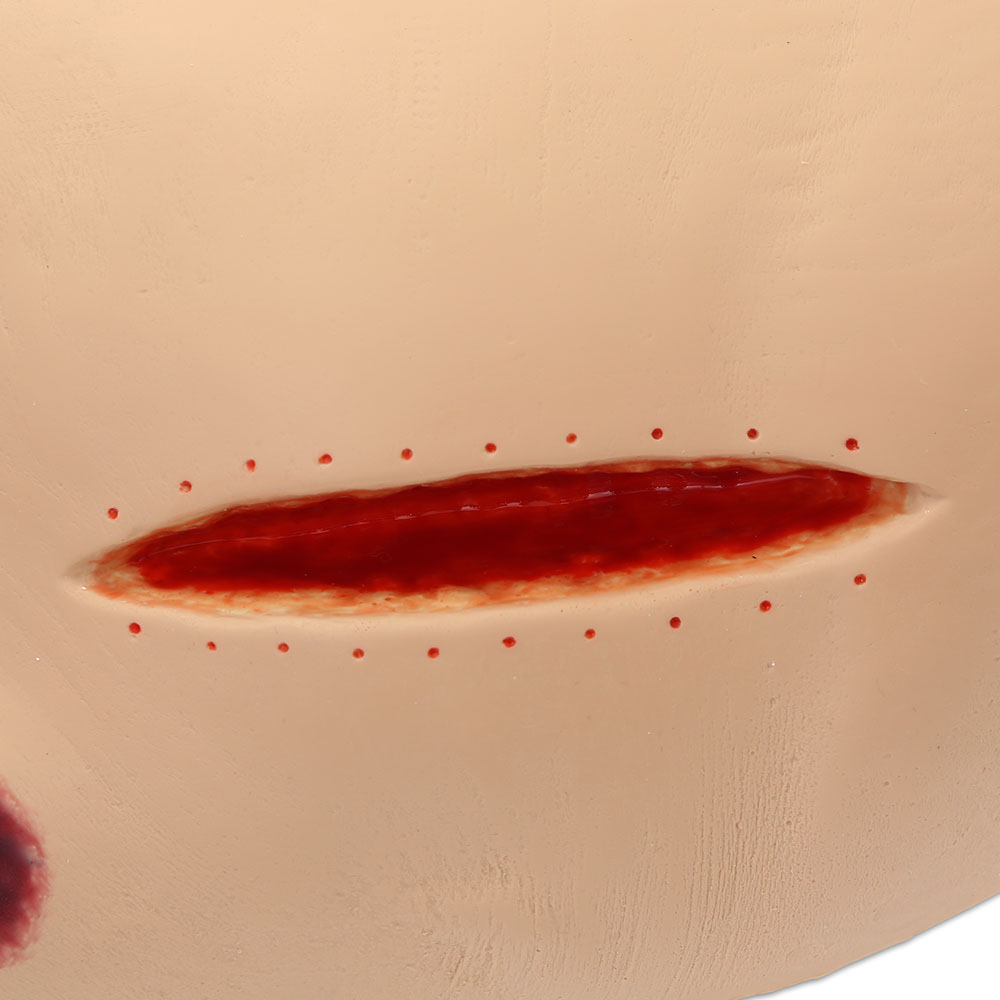

The Seymour II™ Wound Care Model is a highly realistic pressure injury simulator moulded from a 74-year-old patient. It accurately replicates the look and feel of human tissue and presents a wide range of pressure injuries, including Stages 1–4, DTPI, unstageable wounds, and a dehisced wound for advanced wound care training.

- Great care has been taken to hand paint each wound just as you would see it on a patient for the most life-like patient training scenario

- The Seymour patient simulation model makes it possible to visualize and understand the differences in wounds

- Wound care simulation model displays the following pressure injuries:

- 5 ½” dehisced wound